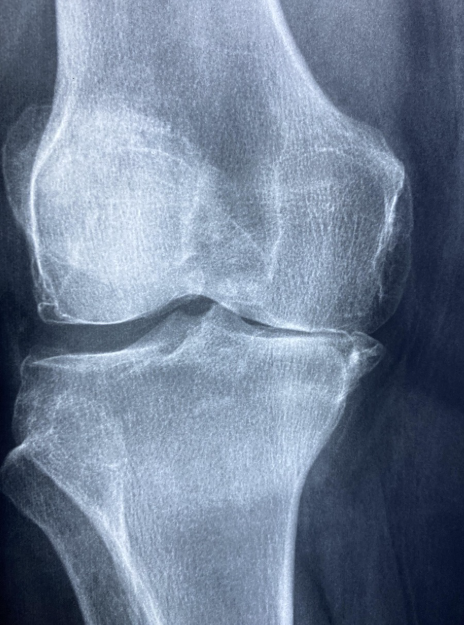

루푸스의 증상은 매우 다양하며 개인마다 양상이 다르게 나타납니다. 증상이 좋아졌다가 악화되는 과정을 반복하는 것이 특징입니다. 초기에는 피로감, 미열, 체중 감소와 같은 비특이적인 증상으로 시작되는 경우가 많아 단순한 컨디션 저하로 오인되기 쉽습니다. 가장 흔하게 나타나는 증상 중 하나는 관절 통증과 관절염입니다. 손목, 손가락, 무릎 등의 관절에 통증과 부기가 발생하며, 아침에 관절이 뻣뻣해지는 증상이 동반되기도 합니다. 류머티즘 관절염과 유사하지만 관절 변형이 적은 것이 특징입니다. 피부 증상도 루푸스의 대표적인 특징입니다. 얼굴에 나비 모양으로 나타나는 홍반은 루푸스를 의심할 수 있는 중요한 신호입니다. 이외에도 햇빛에 노출된 부위에 발진이 발생하거나 탈모, 구강 궤양이 동반될 수 있습니다. 신장 침범이 발생할 경우 단백뇨, 혈뇨, 부종 등이 나타날 수 있으며, 이는 예후에 큰 영향을 미치는 중요한 합병증입니다. 폐나 심장이 침범되면 흉통, 호흡곤란이 발생할 수 있고, 신경계 침범 시 두통, 경련, 인지 기능 저하 등이 나타날 수 있습니다. 루푸스 진단은 단일 검사로 확정되지 않으며, 임상 증상과 혈액 검사, 소변 검사, 영상 검사 등을 종합하여 이루어집니다. 혈액 검사에서는 항핵항체 검사, 항이중가닥 DNA 항체, 항인지질 항체 등이 중요한 지표로 활용됩니다. 염증 수치, 보체 수치 감소 여부, 혈구 감소 소견 등을 함께 평가합니다. 신장 침범이 의심되는 경우에는 신장 조직 검사가 필요할 수 있습니다. 이러한 종합적인 평가를 통해 루푸스 진단이 이루어지며, 조기 진단이 예후 개선에 매우 중요합니다.